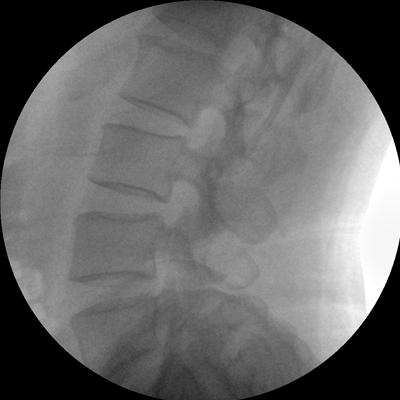

智能化控制系統(tǒng), 讓手術(shù)高效暢捷

四維電動(dòng)運(yùn)動(dòng)控制,平滑定位,使得復(fù)雜角度快速實(shí)現(xiàn)。

專業(yè)的圖像處理系統(tǒng),為您提供高分辨率、高灰階圖像。